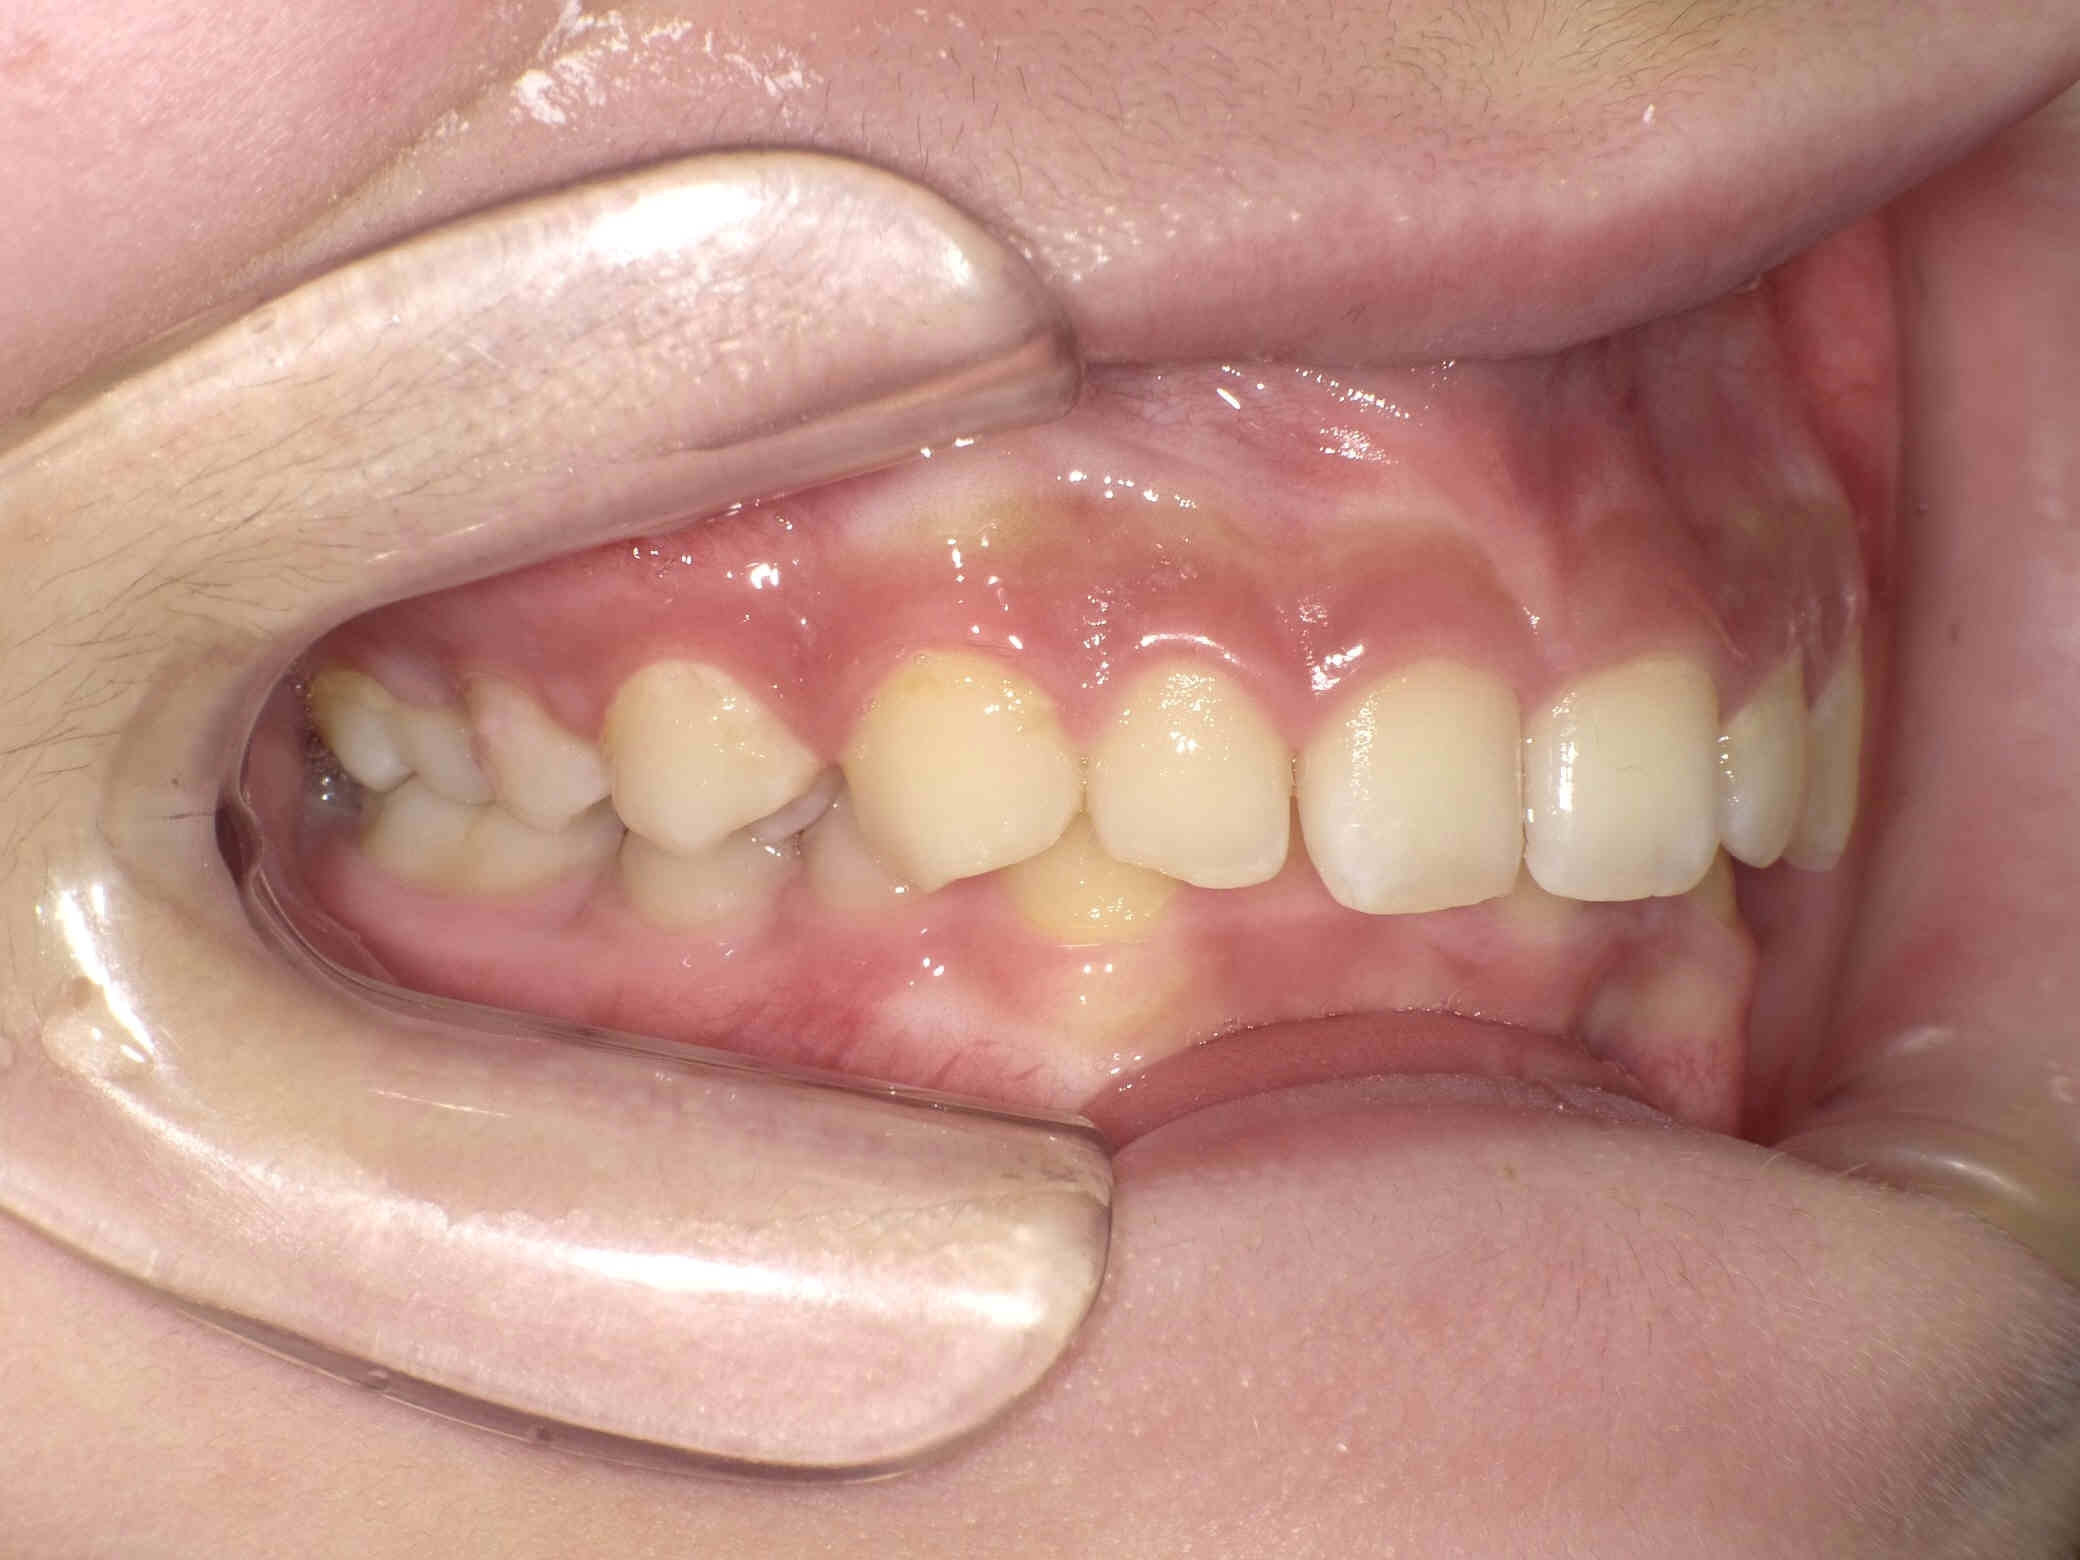

【小児矯正】過蓋咬合と出っ歯

12歳6ヶ月〜スタートです。

やや出っ歯傾向で、噛み合わせが深く

歯並びがデコボコな鋏上咬合(はさみじょうこうごう)という状況でした。

今回はご希望のワイヤー矯正で治療を行い、スタートから1年半で美しい歯並びに改善しました。

1年6ヵ月